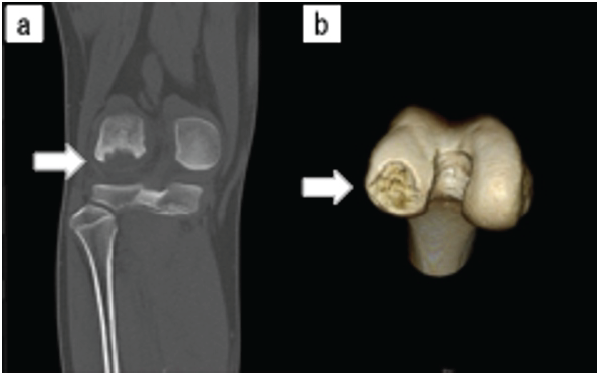

A 13-year-old boy experienced right knee pain while playing football 3 months before his first visit. He was initially diagnosed with a meniscus injury by a local doctor, and he underwent conservative treatment and resumed exercise after 1 month because the pain had subsided. However, the pain recurred, and magnetic resonance imaging (MRI) of the knee joint revealed extensive OCD. He was then referred to our hospital. Physical examination showed a right knee joint range of motion of 0° extension and 140° flexion, with tenderness along the lateral joint line and a positive McMurray test. No ligamentous instability was noted. The Lysholm score was 29 points. X-ray examination at the initial examination revealed flattening of the lateral tibial condyle in the frontal view (Fig. 1a), notch less sign in the lateral view, a loose body in the lateral suprapatellar bursa (Brückl classification stage IV) (Fig. 1b), and a defect posterior to the lateral femoral condyle on the intercondylar fossa view (Fig. 1c). A standing full-length X-ray of the lower limb showed a femorotibial angle of 178° and mechanical axis deviation of 32% (Fig. 1d). Computed tomography indicated a free body measuring 24 mm length and 26 mm width, consistent with a bony defect posterior of the lateral femoral condyle (Fig. 2).

Figure 1: (a) Simple X-ray image showing a flattened lateral tibial condyle (white arrow) in the frontal view. (b) notch less sign (black arrow) in the lateral view. (c) A free body (white arrowhead) in the lateral supracondylar sac and a defect posterior to the lateral femoral condyle (black arrowhead) in the intercondylar fossa radiograph. (d) A full-length standing X-ray of the lower limb showing a femorotibial angle of 178° and mechanical axis deviation of 32%.

Figure 2: (a) Computed tomography image (coronal section) showing a bone defect posterior to the lateral femoral condyle (white arrow). (b) Three-dimensional computed tomography image showing the size of the bone defect posterior to the lateral femoral condyle, measuring 24 mm in length and 26 mm in width.